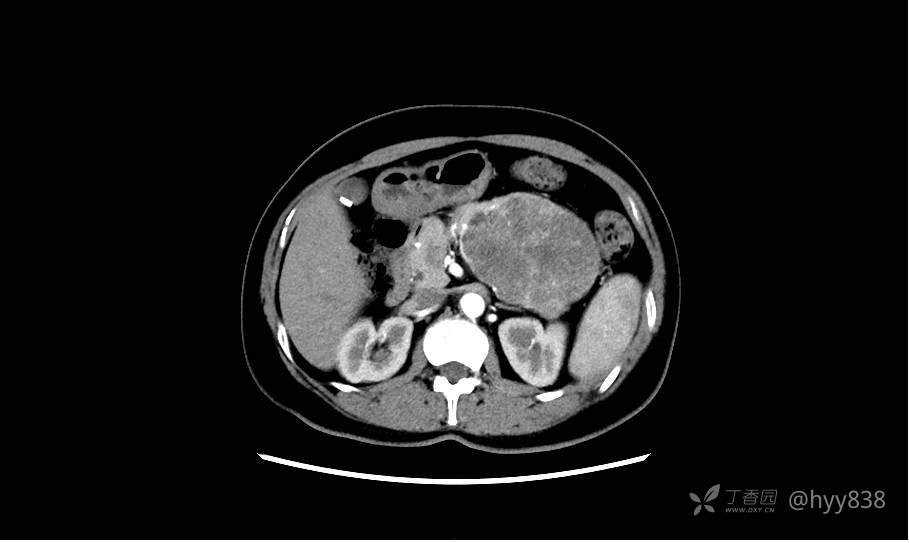

胰腺增强动脉期